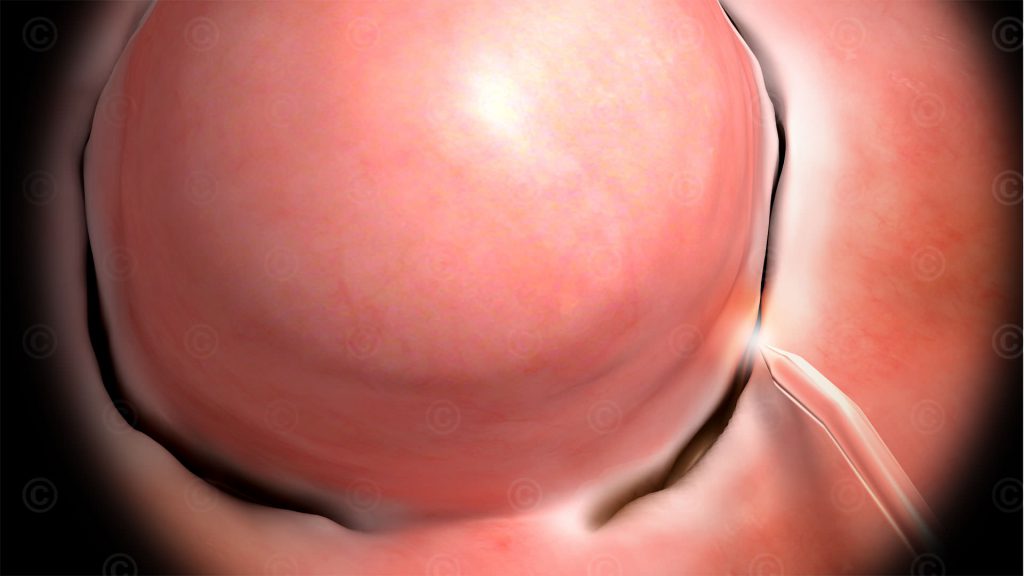

Animation Entfernung Myom mittels Gebärmutterspiegelung

Illustrationen der hysteroskopischen Entfernung eines Myoms aus der Gebärmutter mittels einer Laserfaser.